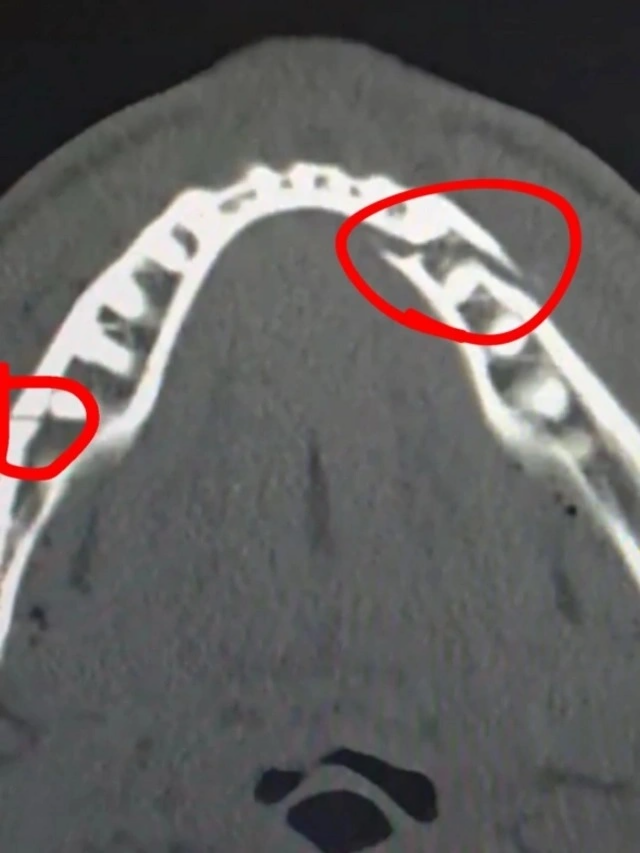

Bloqer Ceyk Pol dünya çempionu Entoni Coşuaya qarşı döyüşdə çənəsinin sındığını bildirib.

"Əla döyüş idi, zövq aldım. Çənəm sınıb. Amma buna baxmayaraq geri qayıdacağam, dünya çempionu olmaq istəyirəm", - deyə Pol döyüşdən sonra rinqdə verdiyi müsahibədə bildirib.

Qeyd edək ki, Mayamidə baş tutan döyüş altıncı raundda Polun nokauta salınması ilə başa çatıb. Pol xəstəxanaya getdiyi üçün döyüşdən sonrakı mətbuat konfransında iştirak etməyib.